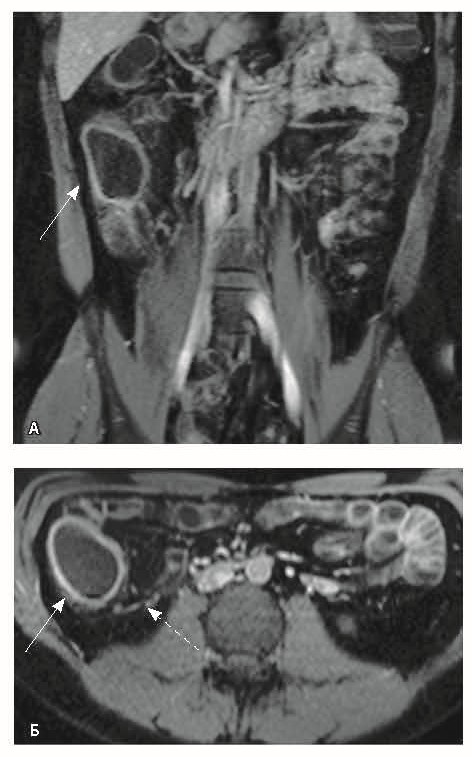

Назначена ГИБТ адалимумабом (препарат Хумира) по стандартной схеме 160 мг п/к (неделя 0), 80 мг п/к (неделя 2) с последующим плановым поддерживающим режимом 40 мг п/к каждые 2 недели. Через 9 месяцев установлена эндоскопическая ремиссия, однако сохранялась концентрация фекального кальпротектина более 2000 мкг/г. Через год жалобы возобновились, тогда же впервые была выявлена задняя анальная трещина. Выполнена магнитно-резонансная энтерография, обнаружены воспалительные изменения, характерные для БК (рис. 2 и 3).

Рис. 2. Магнитно-резонансная энтерография, Т2-взвешенное изображение: А, В – фронтальная проекция; Б – аксиальная проекция. Наблюдается отсутствие гаустрации в восходящем отделе ободочной кишки, утолщение ее стенки до 5 мм (стрелка), снижение магнитно-резонансного сигнала от прилежащих отделов клетчатки, ее неоднородность (пунктирная стрелка), увеличение лимфатических узлов до 6 см в диаметре по ходу сигмовидной кишки (стрелки)